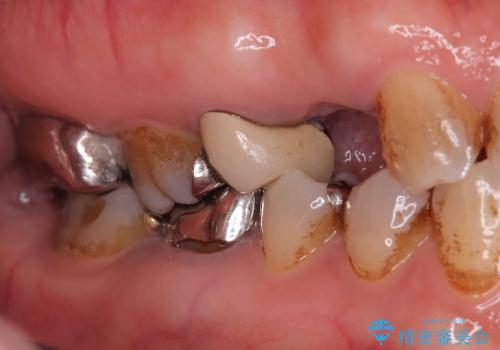

- 「2か月前から歯に違和感があるので診て欲しい」を主訴に来院された患者様です。

被せ物がコア(土台)ごと取れておりかつ根っこも折れてしまっている(歯根破折)状態でした。